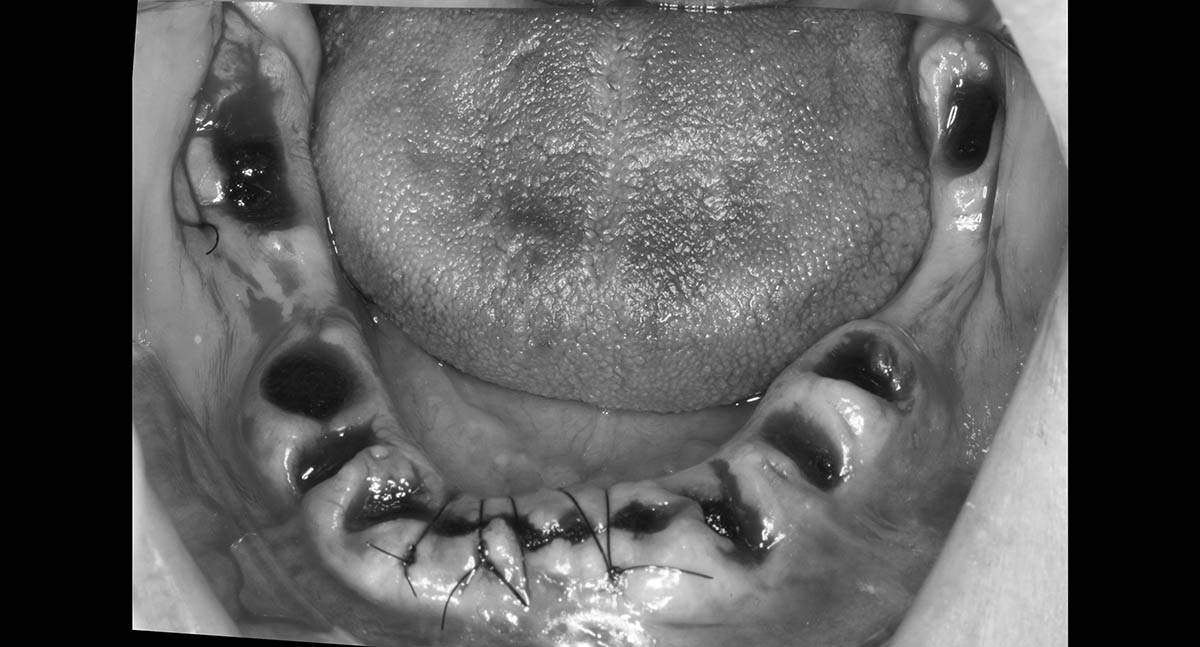

После коррекции десен врач закрепляет ткани швами, что стабилизирует их в новом положении и поддерживает правильную форму. Это обеспечивает оптимальное приживание трансплантированных тканей и снижает риск осложнений.

Швы после пластики десен обычно снимают спустя 7-14 дней после операции. Точный срок может варьироваться в зависимости от конкретной процедуры и индивидуальных особенностей пациента. Наш хирург или пародонтолог предоставит точные указания по времени снятия швов на основе вашего состояния заживления.